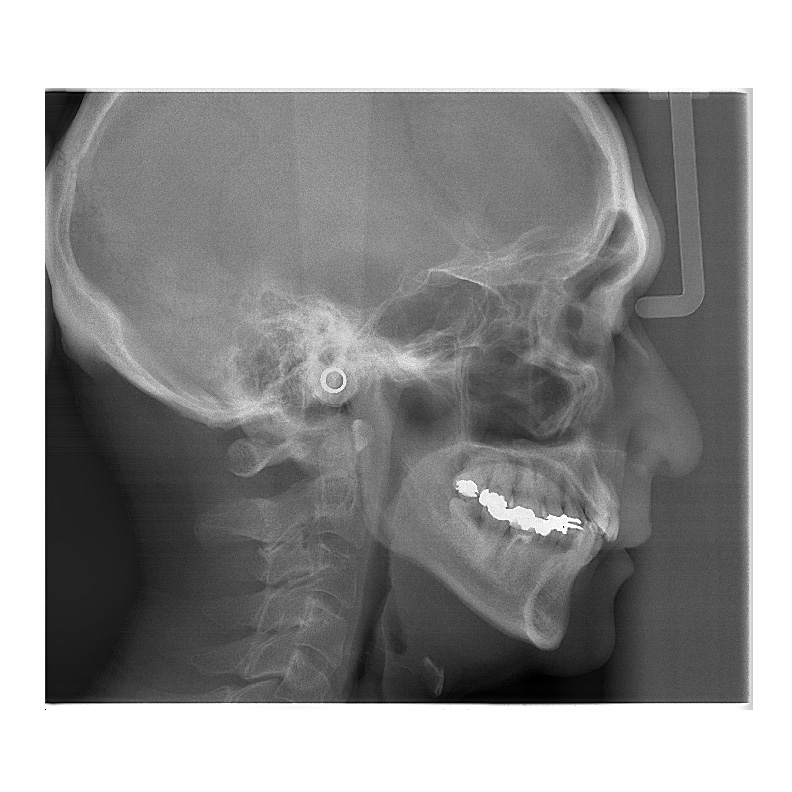

2 VERAVIEW (X800)_CP S(F40) M(R100) L(F150)

Information / DemoPanorama 3D - FOV Up bis zu: Ø 150 X H 140